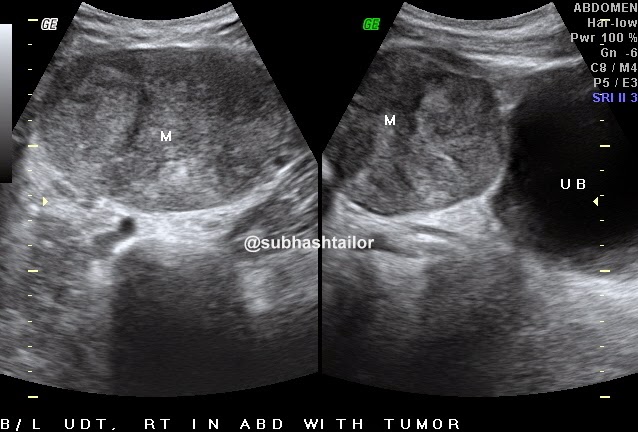

( Figure 1

) - Sagittal US image shows

inhomogenic iso to hypoechoic mass like lesion

( two small arrows )

involving upper pole of right testis

( Figure 2

) -

Color Doppler Us image of same testis shows absent color flow signals in

the abnormal area s/o infarct , and

normal blood flow signals in rest of the testis .

8 to 11 MHZ. linear probe with small parts setting . The grayscale ultrasound

examination revealed a focal enlarged inhomogenic area of iso to hypoechoic echogenisity at upper pole of right testis ( figure 1 ) .

The CDUS failed to show any color flow signals within the mass but color flow

signals were noted normal in rest of the testicular parenchyma ( figure 2 ) . No any calcific focus or cystic change noted

within lesion . No any other ultrasound evidence of epididymoorchitis was present

. The possibility of an acute segmental testicular infract was made rather then

a tumor because of absent color doppler signals in the focal abnormal area .